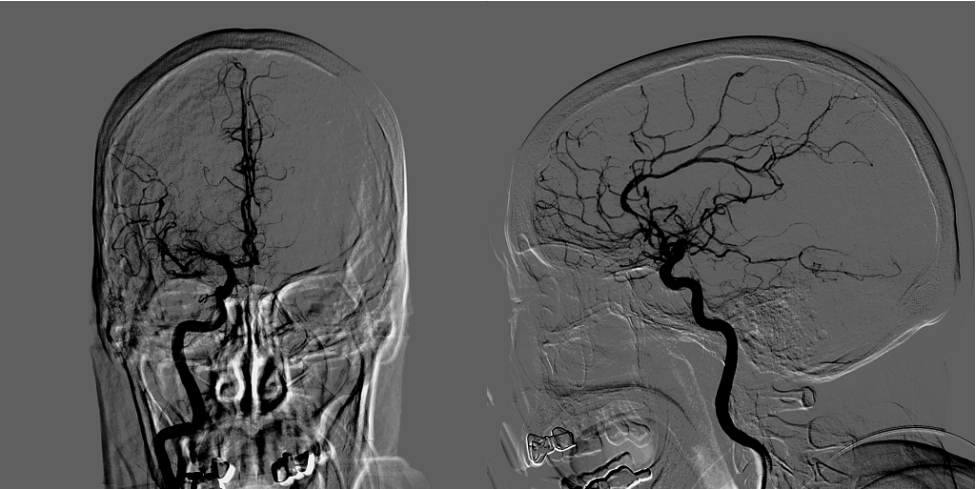

结 果

梗死合并少量出血,暂不给与抗凝抗血小板药物,给与脱水、营养神经、清除脑自由基、改善循环、补液营养支持以及抗感染等药物治疗。

术后5月复查CTA显示右侧颈内动脉及大脑中血流通畅。

术后评估

术后24h:NIHSS评分12分;

术后1周:NIHSS评分9分;

术后3月:mRS评分2分。